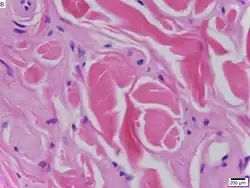

Dado que es la enfermedad de Urbach-Wiethe es una afección autosómica recesiva, los individuos pueden ser portadores de la enfermedad sin mostrar síntomas. La causa de la enfermedad se de a la pérdida de función por la mutación del cromosoma 1 en 1q21, el gen de la proteína de la matriz extracelular 1 (ECM1).[12] Los síntomas dermatológicos se producen por la acumulación de material hialino en la dermis y el engrosamiento de la membrana basal de la piel.[9] La enfermedad de Urbach-Wiethe se diagnostica normalmente por sus manifestaciones dermatológicas clínicas, particularmente las pápulas perladas en los párpados. El descubrimiento de la mutación en el gen ECM1 ha permitido el uso de las pruebas genéticas para confirmar el diagnóstico clínico inicial. La tinción de ácido peryódico de Schiff (PAS) y la tinción inmunohistoquímica también pueden usarse para el diagnóstico[6][13]